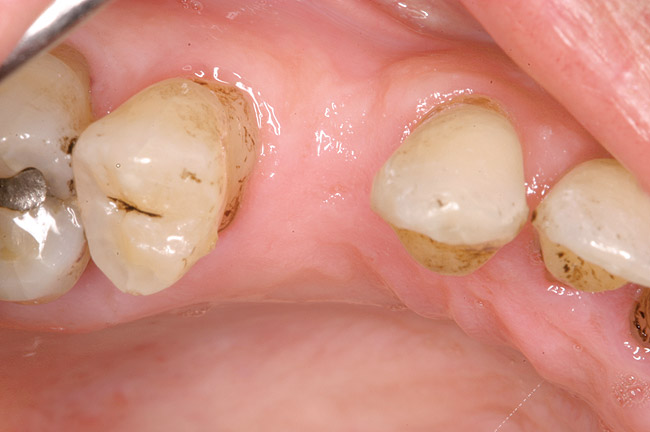

In treatment planning, the decay rate of the patient’s teeth, including the endodontic status of the individual tooth, becomes an important factor when considering long-term outcomes. In the pictured case (Figure 5), tooth No. 11, which previously had been treated endodontically, had recurrent decay and tooth No. 12 had advanced decay with endodontic involvement. In less than 30 days, recurrent decay that reaches the endodontic fill through a leaky restoration (temporary or not), ill-fitting crowns, or broken fillings can re-infect the entire length of the root canal system in a previously endodontically treated tooth.22 Therefore, saving a previously endodontically treated tooth, as in this case, may involve endodontic re-treatment, which can be a deciding factor for tooth preservation.

Figure 5  Recurrent decay of teeth Nos. 11 and 12. Note the proximity of the decay on both teeth to the osseous crest.

Figure 5